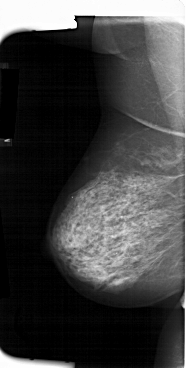

A_1384_1.LEFT_MLO

LEFT_MLO LINES 6616 PIXELS_PER_LINE 3331 BITS_PER_PIXEL 12 RESOLUTION 43.5 NON_OVERLAY